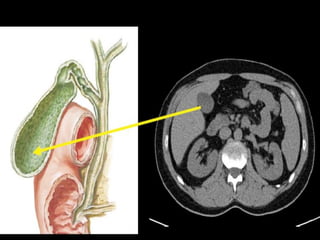

Gallbladder :

 lies in a fossa on the visceral surface of the liver to the right of

the quadrate lobe.

 It stores and concentrates bile, which enters and leaves through

the cystic duct. The cystic duct joins the common hepatic duct

to form the common bile duct.